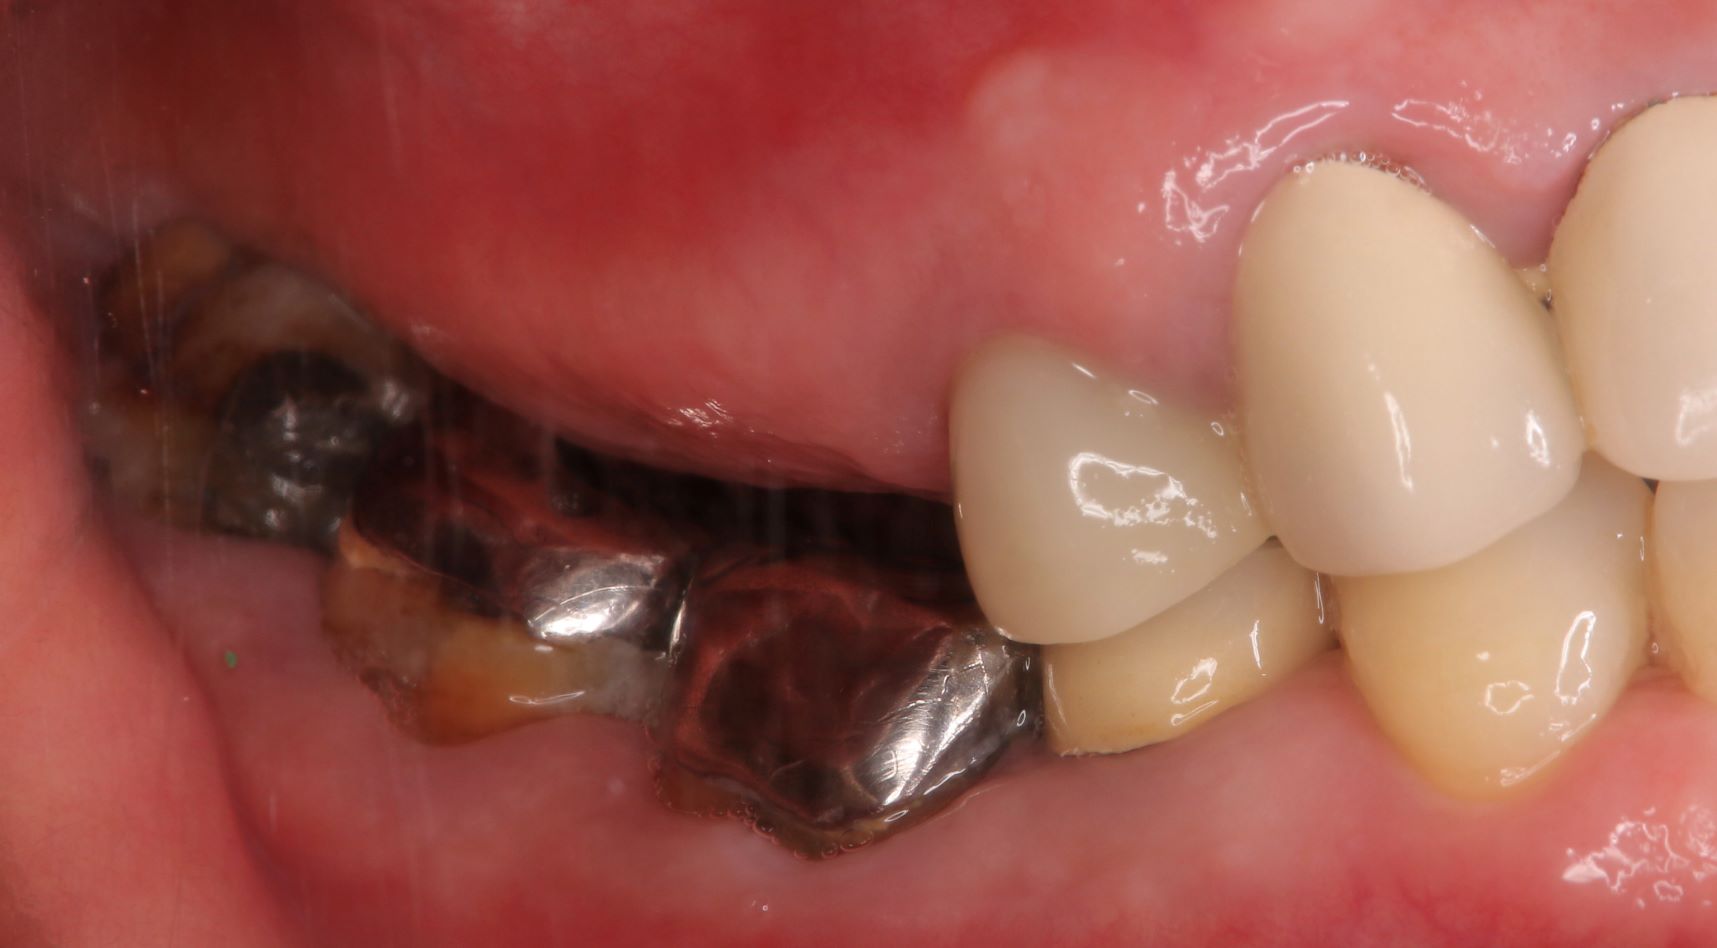

case 03.

BEFORE

AFTER

咀嚼機能の回復を希望し来院された。

(リスク)